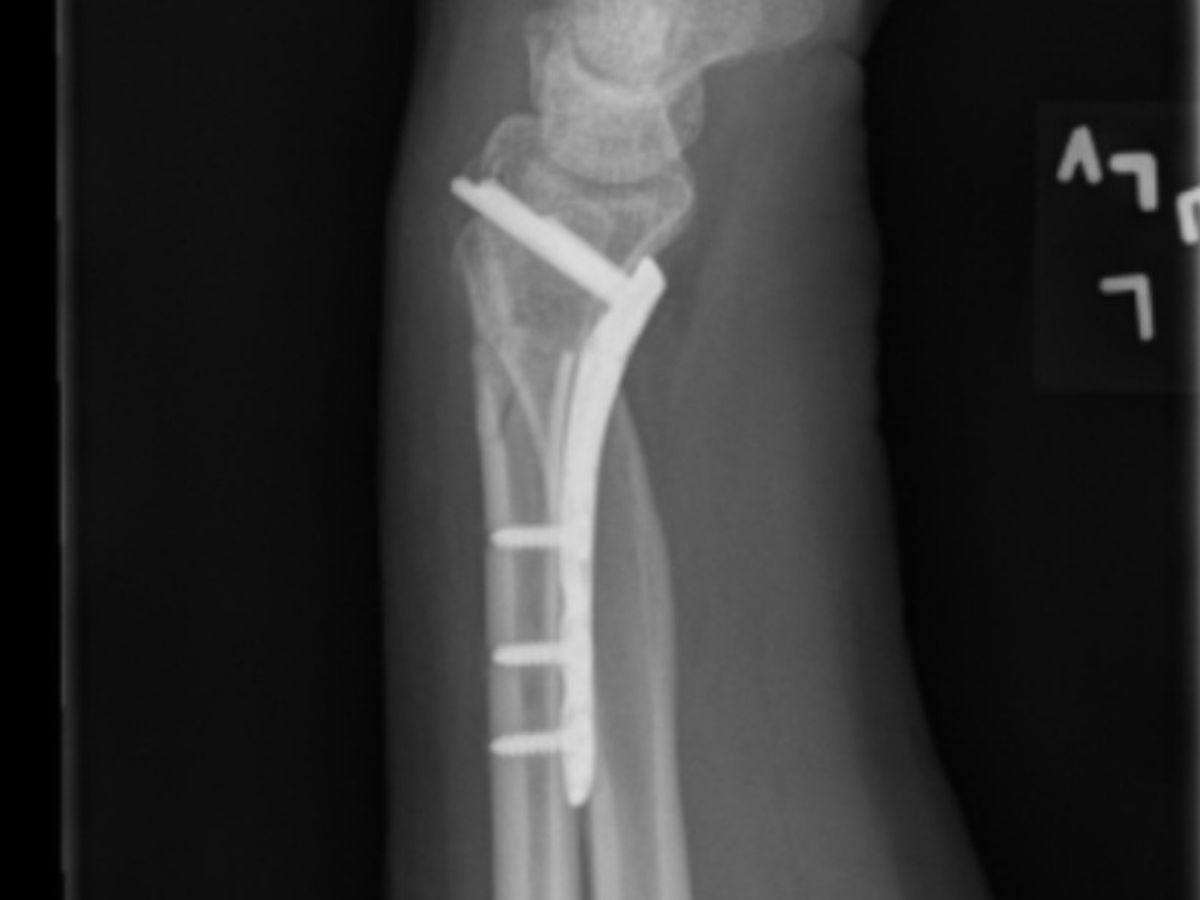

My name is Kelli Scharping. I am a full-time, self-employed Massage Therapist and Reflexologist and proud owner of a thriving practice. On April 9th I fell and broke both bones of my left forearm. In order to ensure no deformity moving forward, and full strength recovery, on April 12th I had surgery to adhere a titanium plate to my radial bone, as that one had broken quite crookedly!